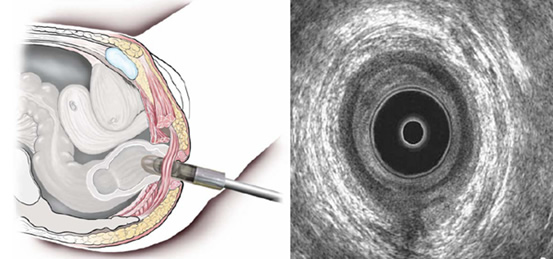

Τα περισσότερα περιπρωκτικά αποστήματα και συρίγγια διαγιγνώσκονται και, τελικά, αντιμετωπίζονται με βάση την κλινική εξέταση. Σε ορισμένες περιπτώσεις, απεικονιστικές μελέτες μπορούν να βοηθήσουν στη διάγνωση ή στη χαρτογράφηση του πόρου του συριγγίου. Σήμερα, τόσο το δύο διαστάσεων, όσο και το τριών διαστάσεων ενδοπρωκτικό υπερηχογράφημα είναι μία πολύ αποτελεσματική δοκιμασία στη διάγνωση ενός βαθιά ευρισκόμενου και δύσκολα αντιληπτού στη δακτυλική εξέταση περιπρωκτικού αποστήματος, στον εντοπισμό μίας πεταλοειδούς επέκτασης του αποστήματος, και στην οριοθέτηση της διαδρομής ενός συριγγίου. Το υπερηχογράφημα μπορεί να συνδυαστεί με έγχυση υπεροξειδίου του υδρογόνου μέσα στην πορεία του συριγγίου (μέσω του εξωτερικού ανοίγματος του) προκειμένου να αυξηθεί η ακρίβεια της εξέτασης.

Το ενδοπρωκτικό υπερηχογράφημα